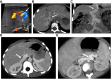

Congenital portosystemic shunts are often associated with systemic complications, the most challenging of which are liver nodules, pulmonary hypertension, endocrine abnormalities, and neurocognitive dysfunction. In the present paper, we offer expert clinical guidance on the management of liver nodules, pulmonary hypertension, and endocrine abnormalities, and we make recommendations regarding shunt closure and follow-up.